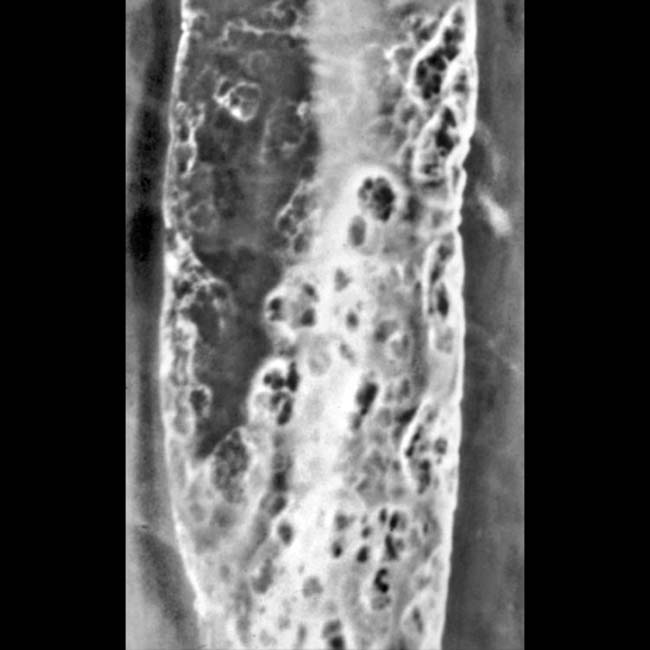

Histopathology Esophagus --Herpes esophagitis - YouTube

Histopathology Esophagus --Herpes esophagitis - YouTube from i.ytimg.com